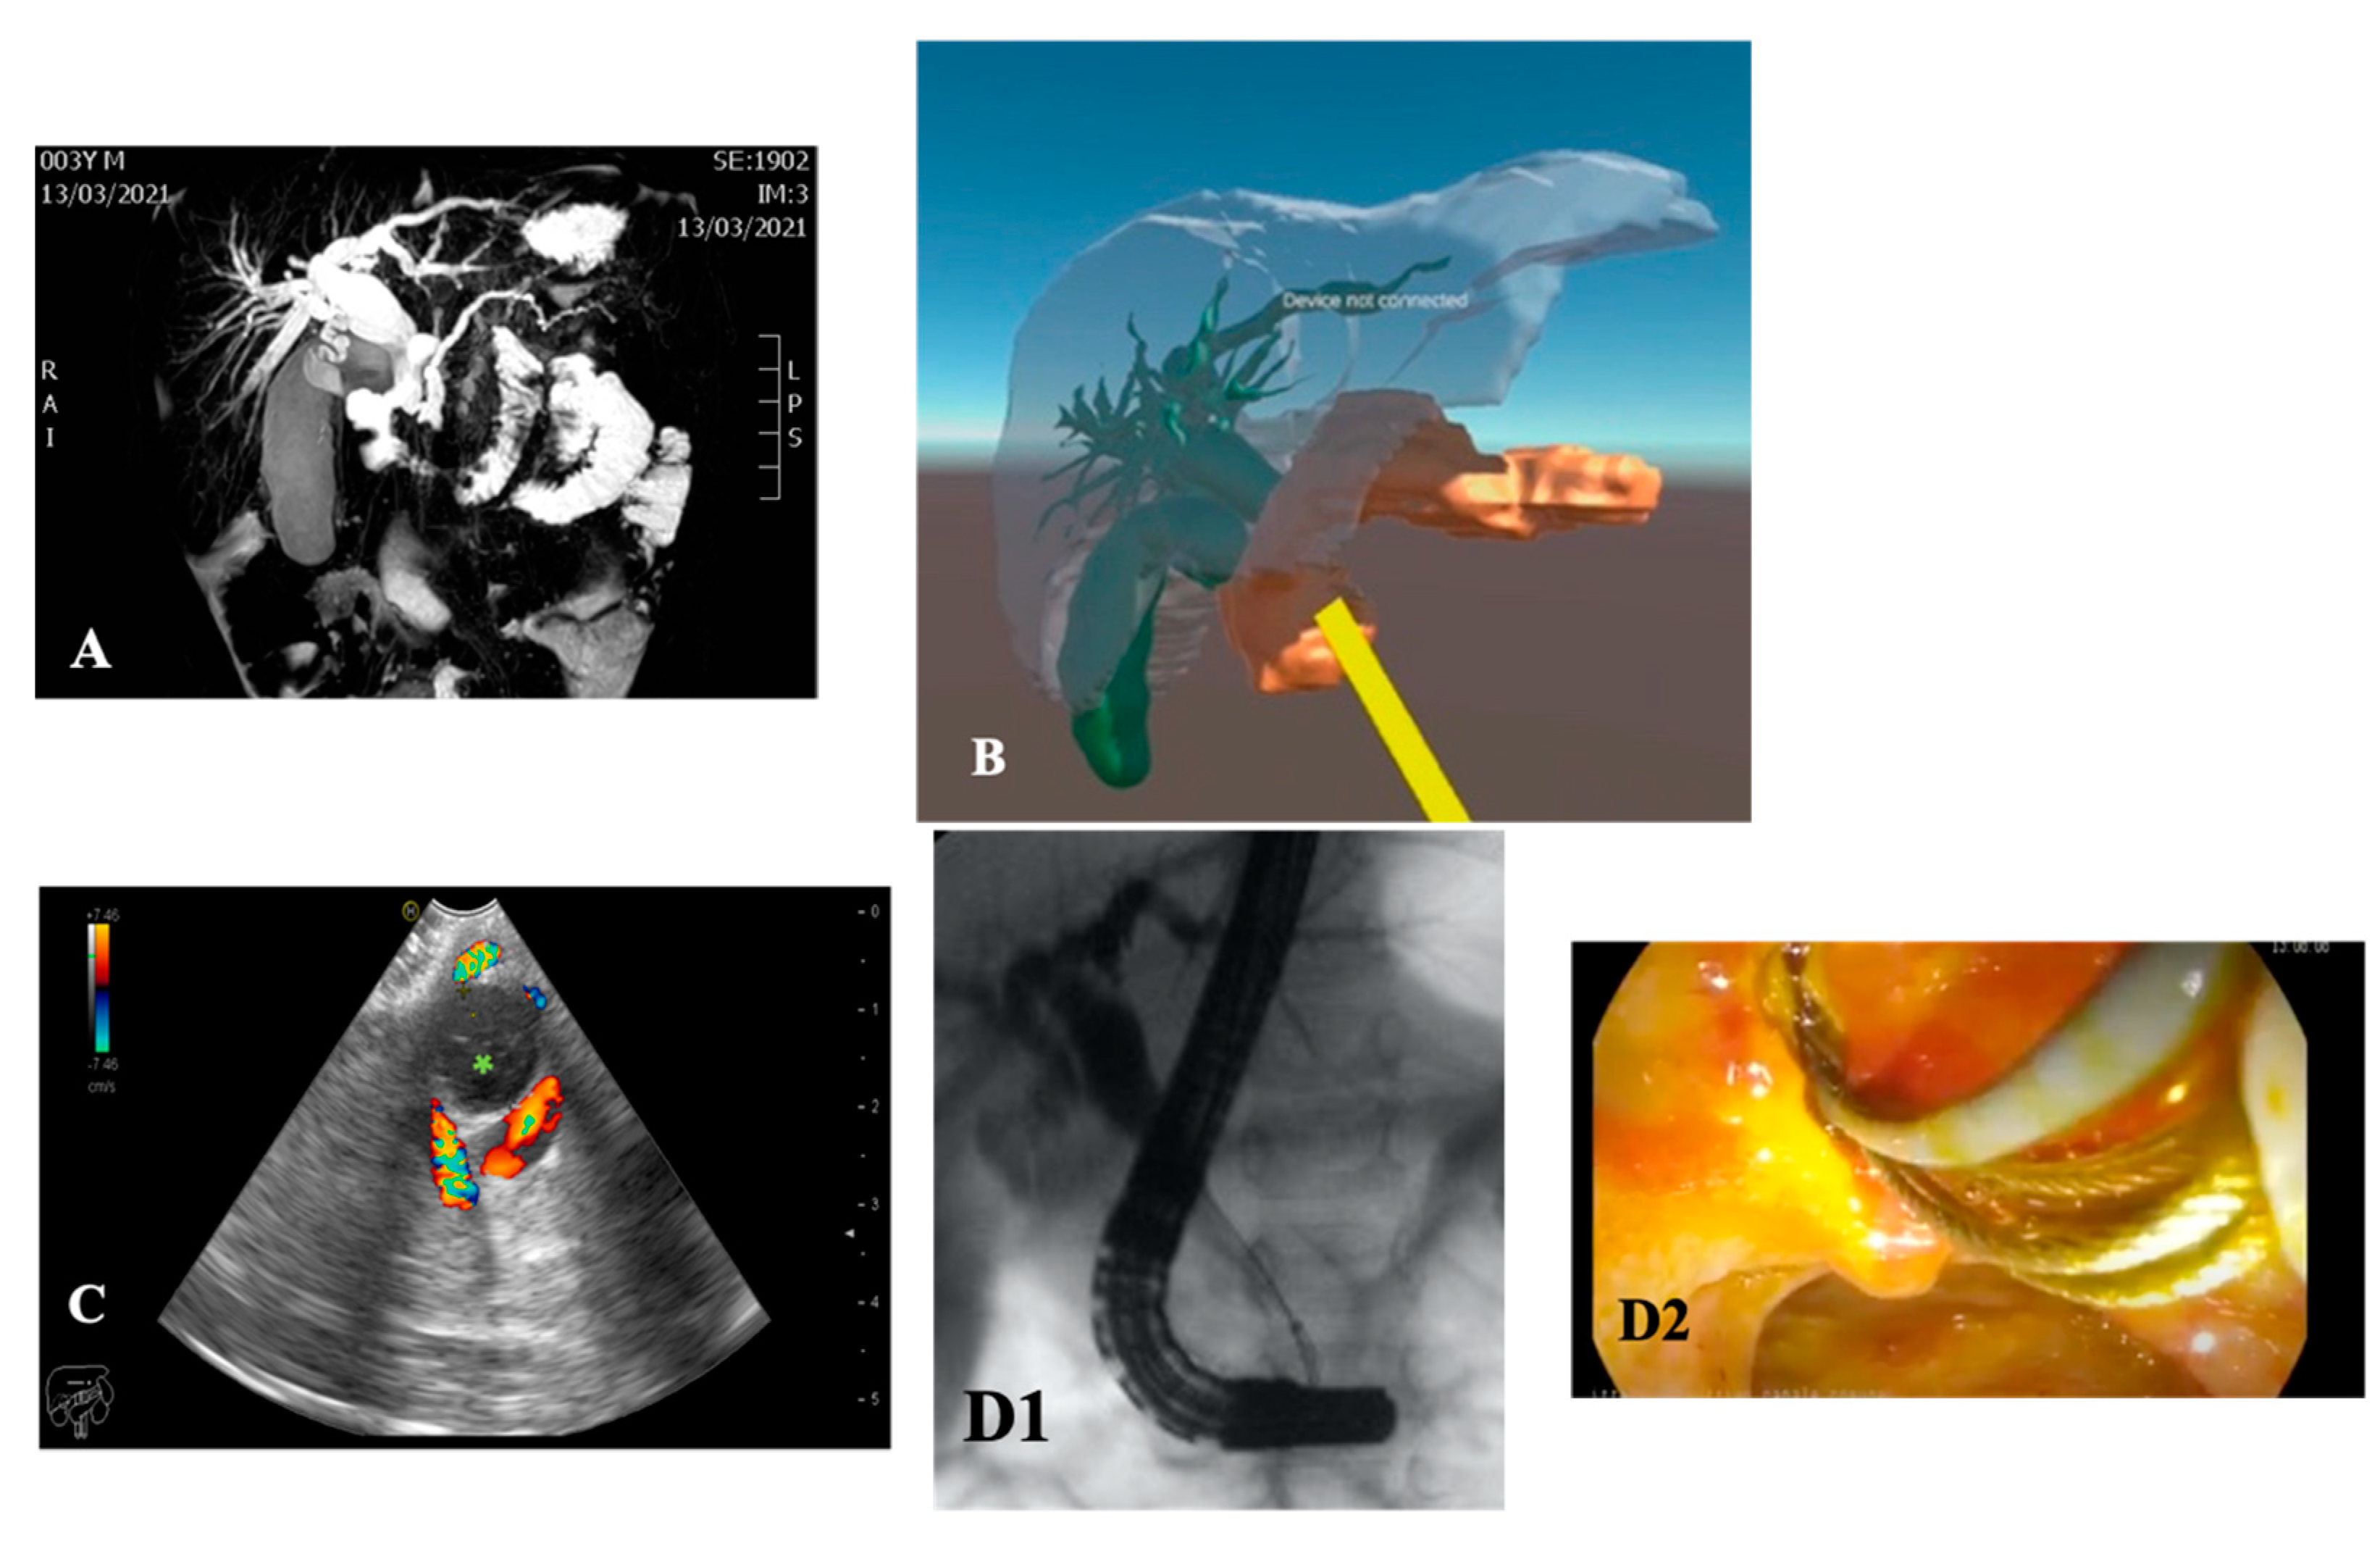

| Patients age, weight | Female 192 months 60 kg | Male 55 months 14 kg | Male 120 months 27 kg | Male 8 months 9 kg |

| Symptoms | Acute pancreatitis, pain in right hypochondrium | Icterus, pancreatitis | Chronic pancreatitis with choletithiasis, genetic-based | No |

| Diagnosis (prenatal evaluation yes/no) | Cholelithiasis and choledocholithiasis in duodenal atresia (duodeno-jejuno anastomosis at birth) and pancreas divisum (yes) | Choledochal cyst (Todani I) and choledocholitiasis (no) | Mutation of the gene PRSS1, Cholelitiasis, pancreatic duct duplication (no) | Gallbladder duplication Annular pancreas Duodenal duplication (yes) |

| Radiological investigations | US, MR, CT Scan, VR HMD | US, Cholangio MR | US, X-ray, Cholangio MR, CT, VR HMD | US, Cholangio MR, CT |

| Endoscopic instrumentation | EG-3870UTK Linear-Array Ultrasound Gastroscope | EBUS + Duodenoscope | Duodenoscope, EG-3870UTK Linear-Array Ultrasound Gastroscope | EBUS |

| Management | MIS (laparoscopic cholecisectomy) with LCBDE | 1. ERCP + sphincterotomy + stone removal 2. Open surgery: choledochal cyst removal and Roux-en-Y bilio-digestive anastomosis | 1. EUS + ERCP + stent placement + sphincterotomy + DASE; MIS (laparoscopic cholecystectomy) with LCBDE 2. ERCP and pancreatic stent replacement | MIS (laparoscopic cholecystectomies) with attempted LCBDE (failure for fibrosis) |

| Endoscopic Advantages/Limitations | Anatomical definition ERCP technically impossible for difficulties in reaching the papilla | Diagnostic and therapeutic procedures | Effective biliopancreatic drainage permitted postponed cholecystectomy and pancreatic preservation | Anatomical definition |